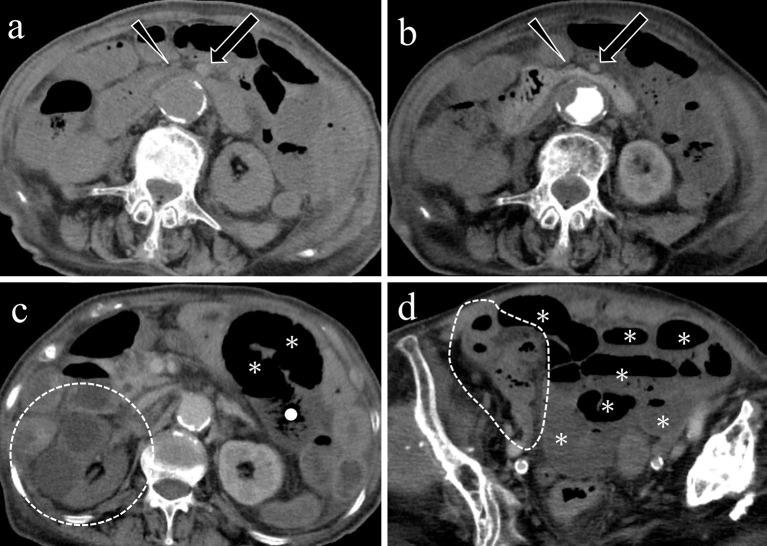

Acute mesenteric ischemia is a life-threatening condition. A comprehensive approach involving a multidisciplinary team to review patient background, clinical history, physical examination, laboratory data, and imaging examination for respective diagnosis of superior mesenteric arterial occlusion, nonocclusive mesenteric ischemia, and superior mesenteric venous occlusion is essential. The most important imaging modality is computed tomography, which is used for diagnosis and for directing therapeutic strategy (e.g., endovascular revascularization, surgical bowel resection, or conservative management). Computed tomography image findings can support triaging of irreversible transmural bowel necrosis compared with reversible ischemic change with reperfusion. In this review article, the computed tomography imaging findings specifically associated with the pathophysiology of superior mesenteric arterial occlusion, nonocclusive mesenteric ischemia, and superior mesenteric venous occlusion are reviewed.

急性肠系膜缺血是一种危及生命的疾病。采用多学科团队的综合方法来审查患者背景、临床病史、体格检查、实验室数据以及影像学检查,以分别诊断肠系膜上动脉闭塞、非闭塞性肠系膜缺血和肠系膜上静脉闭塞至关重要。最重要的影像学检查方法是计算机断层扫描,它用于诊断并指导治疗策略(如血管内血运重建、手术肠切除或保守治疗)。计算机断层扫描图像结果有助于区分不可逆的透壁性肠坏死与可通过再灌注逆转的缺血性改变。在这篇综述文章中,将对与肠系膜上动脉闭塞、非闭塞性肠系膜缺血和肠系膜上静脉闭塞的病理生理学具体相关的计算机断层扫描影像学结果进行综述。